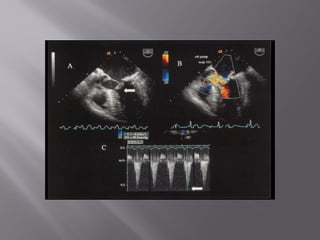

thorough examination of the mitral valve and mitral apparatus and to determine the origin and geometry of the regurgitant jet  long-axis imaging planes are best for determining which mitral leaflet is involved  TTE-PLAX/apical long axis/SHORT AXIS/A4C

Long-axis views of the mitral valve are obtained by imaging from midesophageal TEE planes  Typically, when viewing the left ventricle in a longitudinal plane (120 degrees), the imaging plane intersects the A2/P2 boundary

Imaging at a multiplane angle of about 135 degrees cuts perpendicular to this intercommissural line.  short-axis views also are useful for determining which portion of the anterior or posterior leaflet is involved.

approximately 50 to 60 degrees in most patients, the imaging plane parallel to a line between the commissures, is very useful for determining which portion of the anterior or posterior leaflet is involved.